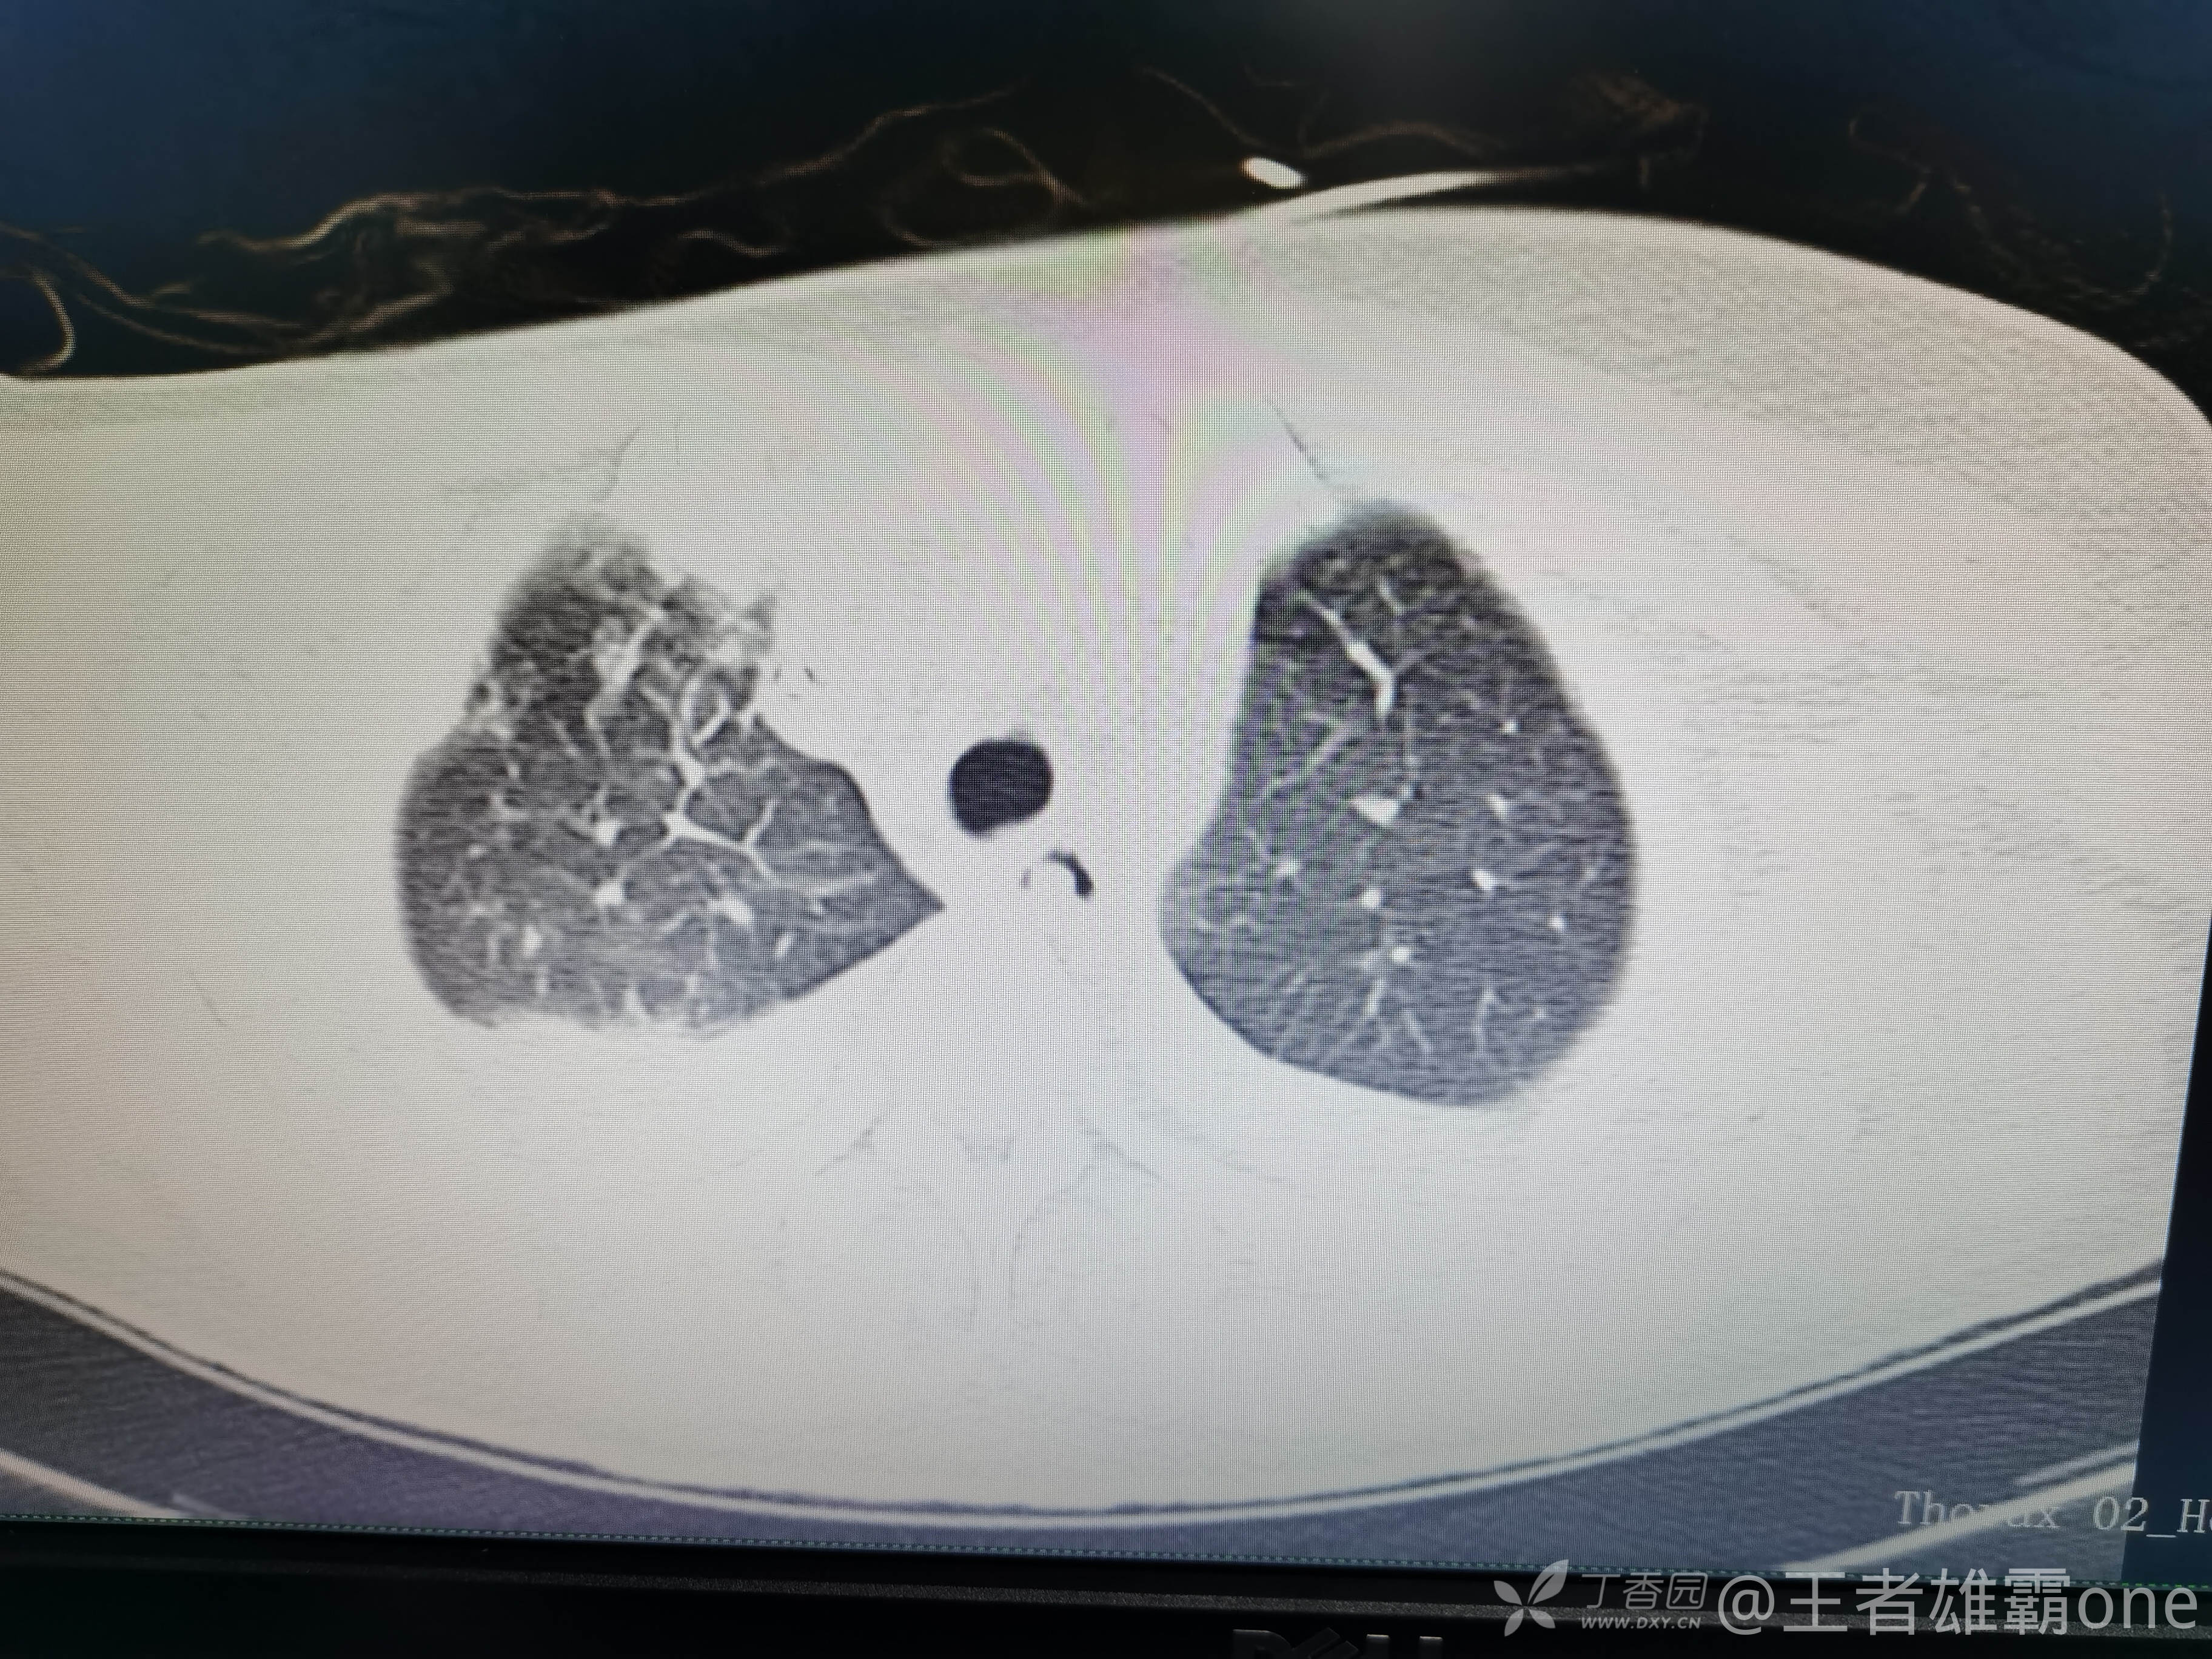

西门开心 推荐63岁女性,因车祸致短暂神志不清、多处疼痛4h入院。简单病史:伤后送至医院急诊就诊。完善头胸腹CT等检查,完善新冠核酸、血常规等化验。血常规提示血红蛋白62g/L。头颅CT提示未见明显外伤性改变。胸腹部CT视频见下:

5.肺挫伤

6.双侧多发肋骨骨折

12.双侧胸腔少量积液